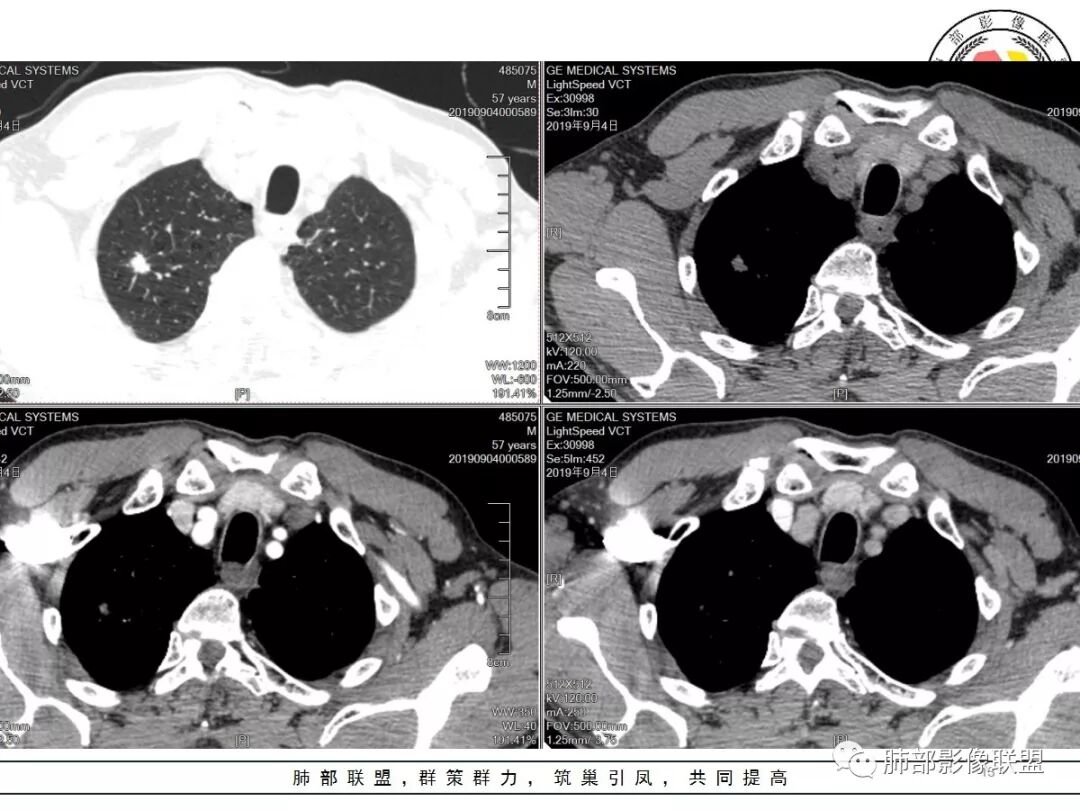

男,57岁,因“体检发现右上肺占位”入院。凝血常规、血常规、肾功能等均未见明显异常。

CT值:

平扫  18                          动脉期  28                      静脉期 41

结核。右上肺结节密度均匀轻度强化,结节边缘清晰有小分叶,周围细长软毛刺,有卫星灶。左上肺近纵隔类似片状结节。

两肺上叶结节影,右肺结节边缘清晰,平直,有胸模牵拉,有卫星灶,强化不明显,左肺结节周边强化,两肺门淋巴结肿大,整体考虑结核。

中年男性,查体发现,右肺肺上叶结节影,边缘平直收缩,周围有软毛刺,有胸膜牵拉,左肺上叶靠近纵隔不规则结节影,边缘平直内收,内有坏死。考虑良性病变可能性大,肺结核。鉴别肺癌合并结核。

中老年男性,体检发现双肺尖结节,边缘长索条,邻近胸膜粘连,病灶收缩力不太强,右肺尖病变周围少许卫星灶,增强后环形强化表现,首先考虑结核,治疗后复查

两上肺(右尖左尖后)都有小结节影,右肺尖结节边缘可见卫星灶,结节边缘平直凹陷、长毛刺,部分膨隆,增强扫描右肺尖结节强化不明确;左肺尖后段结节边缘平直凹陷,增强见环形强化。考虑结核可能性大,右上肺注意鉴别腺癌。

老年男性,体检发现右上尖段及左上尖后段不规则结节影,右上尖段结节边缘长毛刺、似见卫星灶、局部胸膜牵拉,增强无明显强化。左上结节环形强化,考虑结核。老年男性,肺气肿背景,注意排除右上肺腺癌。

倾向二元,左肺上叶病灶环形强化支持结核,右肺上叶结节平直、部分稍膨隆,胸膜牵拉征,部分毛刺粗短、支气管似乎边缘截断,临近小叶间隔增厚,延迟强化,密度似乎不均匀,内见小点状坏死,腺癌放前面,炎性放待排。

老年男性,体检发现,右肺上叶尖段类圆形结节

小叶中心型肺气肿背景,一般提示吸烟

周围有类似小结节

小斑片

根据周围常规:我们要考虑结核的可能

我们再看右肺上叶这个较大病灶主体

类圆形,浅分叶

胸膜凹陷

血管纠集

局部凸起

强化幅度超过20HU

边缘平直